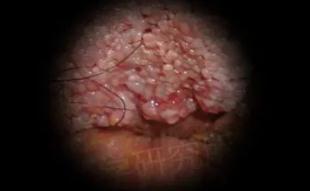

感染hpv病毒的潜伏期大概为2-3个月,在X生活后,发现自己的私处有长异样的疣体,初期是如图所示,米粒大小的丘疹,在短时间内会增大,互相融合,呈菜花状、鸡冠状的柔软疣体,容易破溃出血,如果感染还会有恶臭散出,一点要尽快治疗。

这是女性早期的小疣体,多长在YD、阴唇、肛门、宫颈内或者是尿道口,早期就是淡红色、柔软的细小丘疹,因为面积不大,所以很容易被忽视,还会感觉外阴瘙痒,疼痛,疣体很脆容易出血……